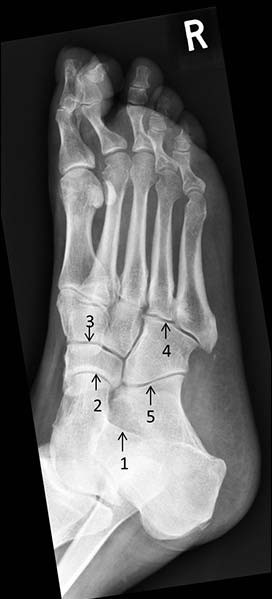

A 55-year-old man with type 2 diabetes mellitus presented with foot swelling and discomfort. He had a peripheral sensory neuropathy attributed to diabetes mellitus. A midfoot Charcot’s arthropathy was suspected, and a plain X-ray was arranged (see image).

Which is the talonavicular joint?

1. 1

2. 2

3. 3

4. 4

5. 5

Answer(s): B